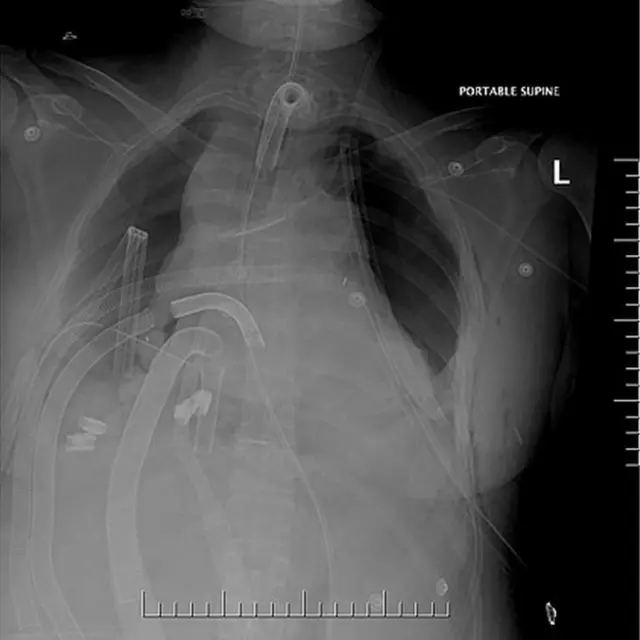

Le conectaron un pequeño pulmón artificial al corazón mientras que otros aparatos oxigenaban y se encargaban de la circulación de su sangre.

Seis días más tarde, le pudieron hacer un trasplante.